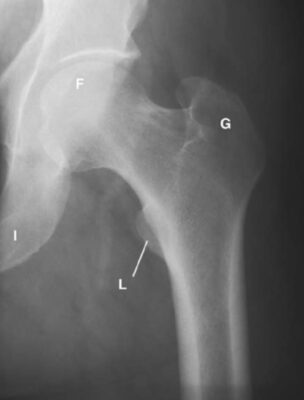

LIÊN HỆ X QUANG

Ghi chú viết tắt:

- F = Femoral head; chỏm xương đùi

- G = Greater trochanter of femur; mấu chuyển lớn xương đùi

- I = Ischium; ụ ngồi

- L = Lesser trochanter of femur; mấu chuyển bé xương đùi